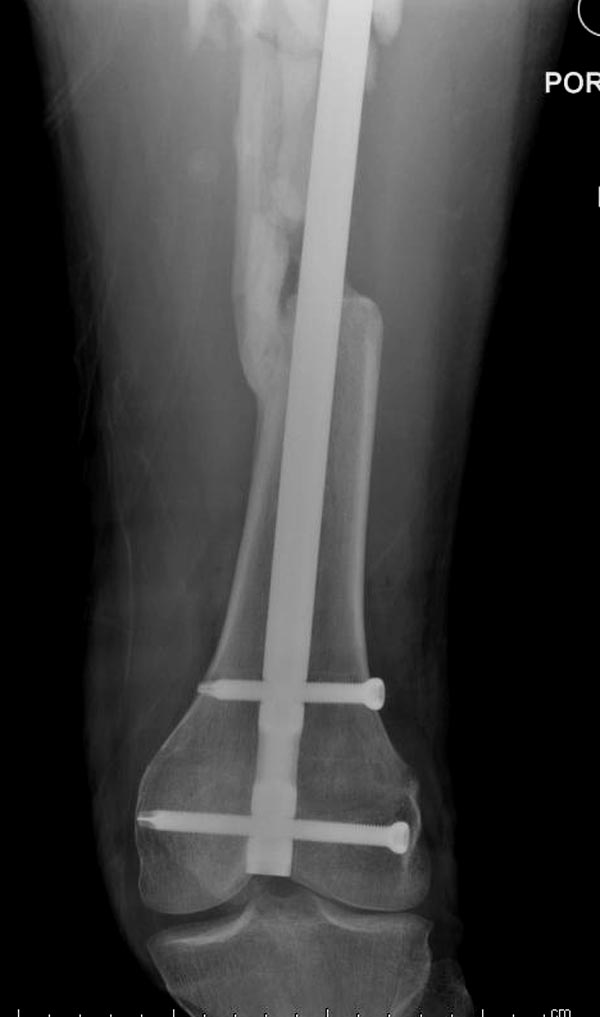

Здесь выставлен ренгенограммы больного, ему 21, травму получил в результате высокоскоростной погони на украденной машине, которая закончилась смертью трех остальных “боевых комрадов”. Начатую коллегой открытую операцию на шейке пришлось закончить мне, установкой винтов и ретроградной фиксацией бедра. Выписка в обычное сроки и наблюдался амбулаторно. Каждый раз напоминали о возможности осложнений ввиде несращения! По истечению 4 месяцев появились признаки варусной деформации. На СТ срезах несращение шейки и бедра. Риминг, замена на более толстый гвоздь и вальгусная остеотомия.

Сразу скажу, что пациент вчера (8.04) прооперирован - артротомия, остеосинтез мыщелков большеберцовой кости канюлированными винтами, открытая репозиция отломков бедренной кости, ретроградный БИОС, остеосинтез надколенника (центральных его отломков) спицами с проволочной петлей. Двухкратная попытка закрытой репозиции шейки на операционном столе после синтеза бедра - абсолютно неэффективна. Учитывая продолжительность и травматичность операции, шейка отложена на 2-й этап. Плечо наверное на 3-й (если вообще делать). Снимки постараюсь предоставить, но чуть позже.